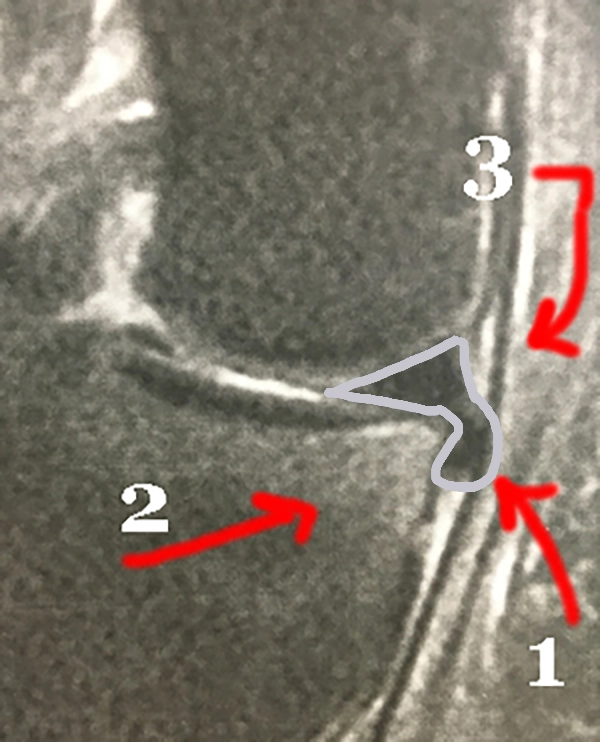

IRM de la Languette méniscale

Les signes sur l'IRM en faveur d'une lésion mécanique, sont la fissure verticale complète et l'amputation (1) de la pointe du triangle méniscal. Le bout du triangle est un morceau du ménisque, qui a migré : la languette.

La languette (1) est retrouvée ici sous le ménisque; elle repousse le ligament interne (3). L'os est un peu blanc (petit oedème osseux) (2) dans l'angle en regard de la languette, témoignant de l'inflammation locale.